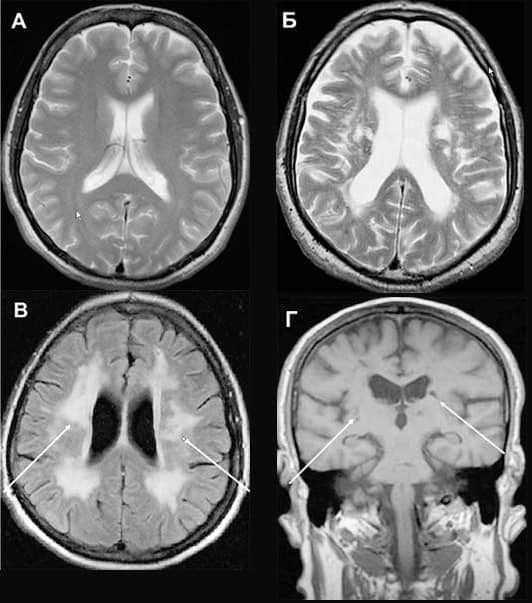

Сосудистые заболевания мозга (фото полученное при МРТ)

Патологические процессы могут носить как врожденный, так и приобретенный характер. Обычно диагноз ставится или на начальной фазе, как правило, в период обострения, но болезнь может иметь хроническое течение.